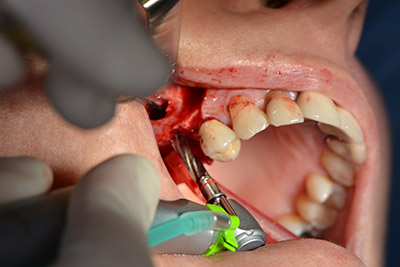

El guiado clásico del corte (crestal, descarga bucal) y la preparación del colgajo mucoperióstico permiten obtener una buena visión global.

En este caso se utilizan implantes Sky (Bredent), cuyo protocolo quirúrgico exige el fresado piloto a unas 1.200 rpm (figura 9).

Las perforaciones siguientes se realizan a una velocidad reducida de 300 rpm. Y es aquí donde se demuestra una de las ventajas de Implantmed. El protocolo quirúrgico puede predefinirse y las diferentes posiciones pueden seleccionarse pisando el pedal hacia la posición "P" (figuras 10 a 11).